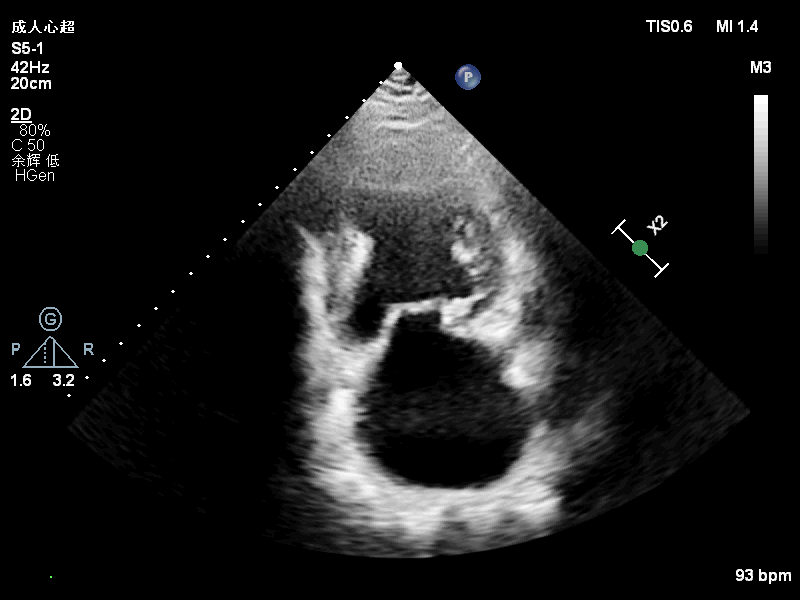

基本情况:63岁男性,患者夜间阵发性呼吸困难半年入院。患者半年前无明显诱因出现夜间平卧位呼吸困难,伴胸闷,无胸痛、大汗,无咳嗽、咳痰等,日常活动不受限。至我院住院查超声心动图提示:二尖瓣后叶P1区+前交界大脱垂,考虑DMR,Carpentier II型,二尖瓣重度关闭不全(重度,4级),左心增大,冠脉造影提示LAD近段80%狭窄,LCX远段70%狭窄,RCA近段75%狭窄,远段70%狭窄,建议患者行外科二尖瓣修复+冠脉搭桥手术治疗,患者拒绝外科手术后出院。出院后患者口服阿司匹林、螺内酯、厄贝沙坦氢氯噻嗪等药物治疗,仍有间断夜间平卧位呼吸困难,为进一步诊治收入院。

入院诊断:心脏瓣膜病,原发性二尖瓣关闭不全,二尖瓣后叶及交界区脱垂 二尖瓣重度关闭不全, 冠状动脉粥样硬化性心脏病, 劳力+自发型心绞痛,心脏扩大,心功能III级(NYHA),高血压,高脂血症

术前超声评估结果

术前超声诊断